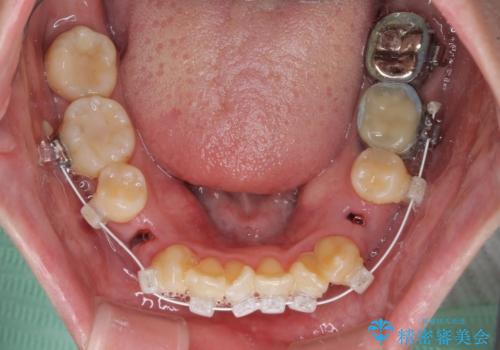

急速拡大装置 狭い骨幅を拡大した上で、顕著なデコボコを改善する抜歯矯正治療

上顎骨よりも下顎骨の幅が広く、更には下顎骨が左側に変位していたため、より良い咬み合わせを達成することを目的として、急速拡大装置を用いて上顎骨を拡大することとしました。

歯根露出が顕著であったため、歯の移動は早く、スムーズに治療を終えられるかと思いましたが、歯槽骨が硬く、治療は長期間に及びました。

過剰に力をかけ続ける事態となり、一部の歯では変色したり、神経が失活したりとトラブルが続きました。